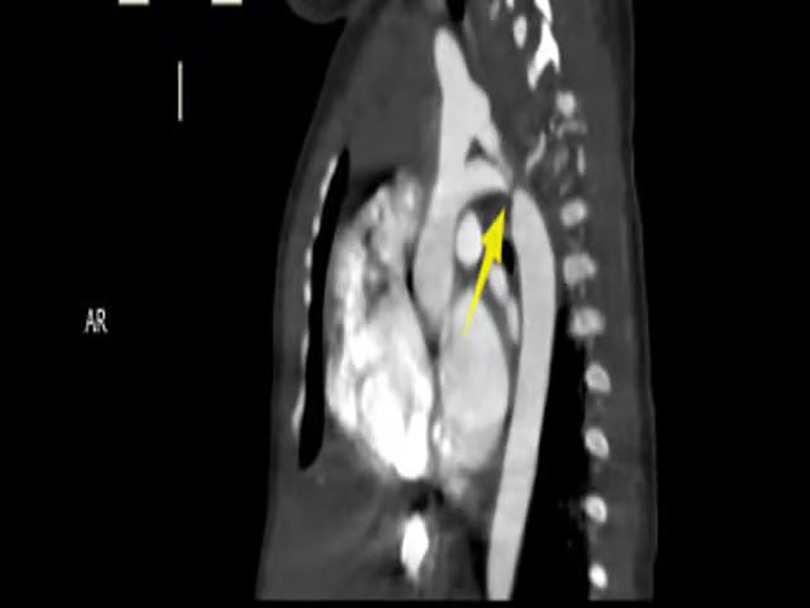

Imaging studies included a chest x-ray showing cardiomegaly and pulmonary congestion, followed by echocardiography, which identified a persistent fifth aortic arch (PFAA) with coarctation (narrowest diameter: 5 mm), an interrupted fourth aortic arch (Figure 1). Color Doppler demonstrating turbulent flow at the coarctation site (peak velocity: 4.1 m/s) (Figure 2). A patent ductus arteriosus (PDA; 3 mm) located between the proximal descending aorta and the pulmonary artery bifurcation, and an atrial septal defect (ASD; 6 × 8 mm), accompanied by reduced left ventricular systolic function (ejection fraction: 49%). Cardiac CT (Figures 3, 4) further confirmed the anatomical details, including a 12 mm gap in the fourth aortic arch and the PFAA's aberrant course.

CT scan showing a sagittal view of the thorax. The image highlights a yellow arrow pointing to the aortic arch, illustrating an area of interest near the spine on the right side.

Figure 3. CTA: persistent fifth aortic arch associated with stenosis (indicated by arrows) and an interrupted fourth aortic arch. The fourth arch was interrupted at the distal end of the left subclavian artery, about 12 mm long. The fifth arch continued with the descending aorta, with a length of about 9 mm and an internal diameter of about 5 m at the proximal end.